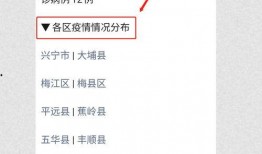

梅州最新爆料消息今天疫情,揭秘病毒传播轨迹与防控措施”

你知道吗?最近梅州又有了新的疫情动态,这可是个大新闻呢!今天,我们就来聊聊这个话题,看看梅州疫情的最新情况。梅州疫情最新进展首先...